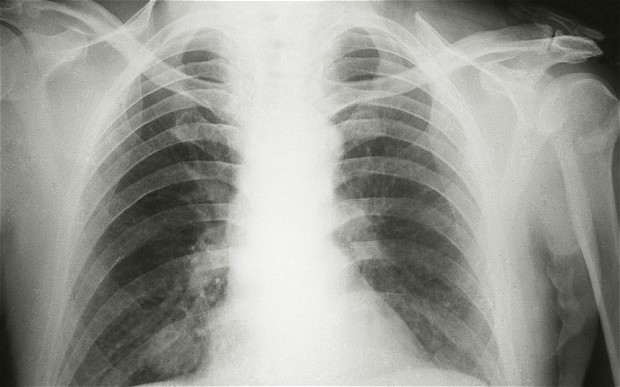

Un bărbat de 53 de ani din India a fost tratat timp de şase luni de pneumonie şi infecţii respiratorii, însă prin intermediul bronhoscopiei medicii au descoperit că în plămânul stâng al bărbatului se afla un os de pui, scrie descopera.ro.

Bărbatul fusese tratat de pneumonie în diferite spitale, informează TimeofIndia. Atunci când a dezvoltat o infecţie severă la plămâni a fost adus în cadrul spitalului Amrita Institute of Medical Sciences, unde o parte din infecţie a fost eliminată cu ajutorul tratamentului.

”Credeam că are o tumoră şi părea că există o umflătură pe plămânul stâng. Prin intermediul bronhoscopiei am început să-i verificăm interiorul plămânului, când am observat existenţa unui os de pui,” a declarat dr.Rajesh V., ce a realizat procedura.

”Osul a fost îndepărtat în timpul procedurii, însă un obiect atât de mare ajunge extrem de rar în plămân,” a adăugat el.

Ciudat este că pacientul nu îşi aminteşte să se fi înecat cu osul sau să tuşească în timp ce mânca pui. Medicii consideră că osul a ajuns în căile respiratorii în urmă cu aproximativ un an.

(Foto: telegraph.co.uk)